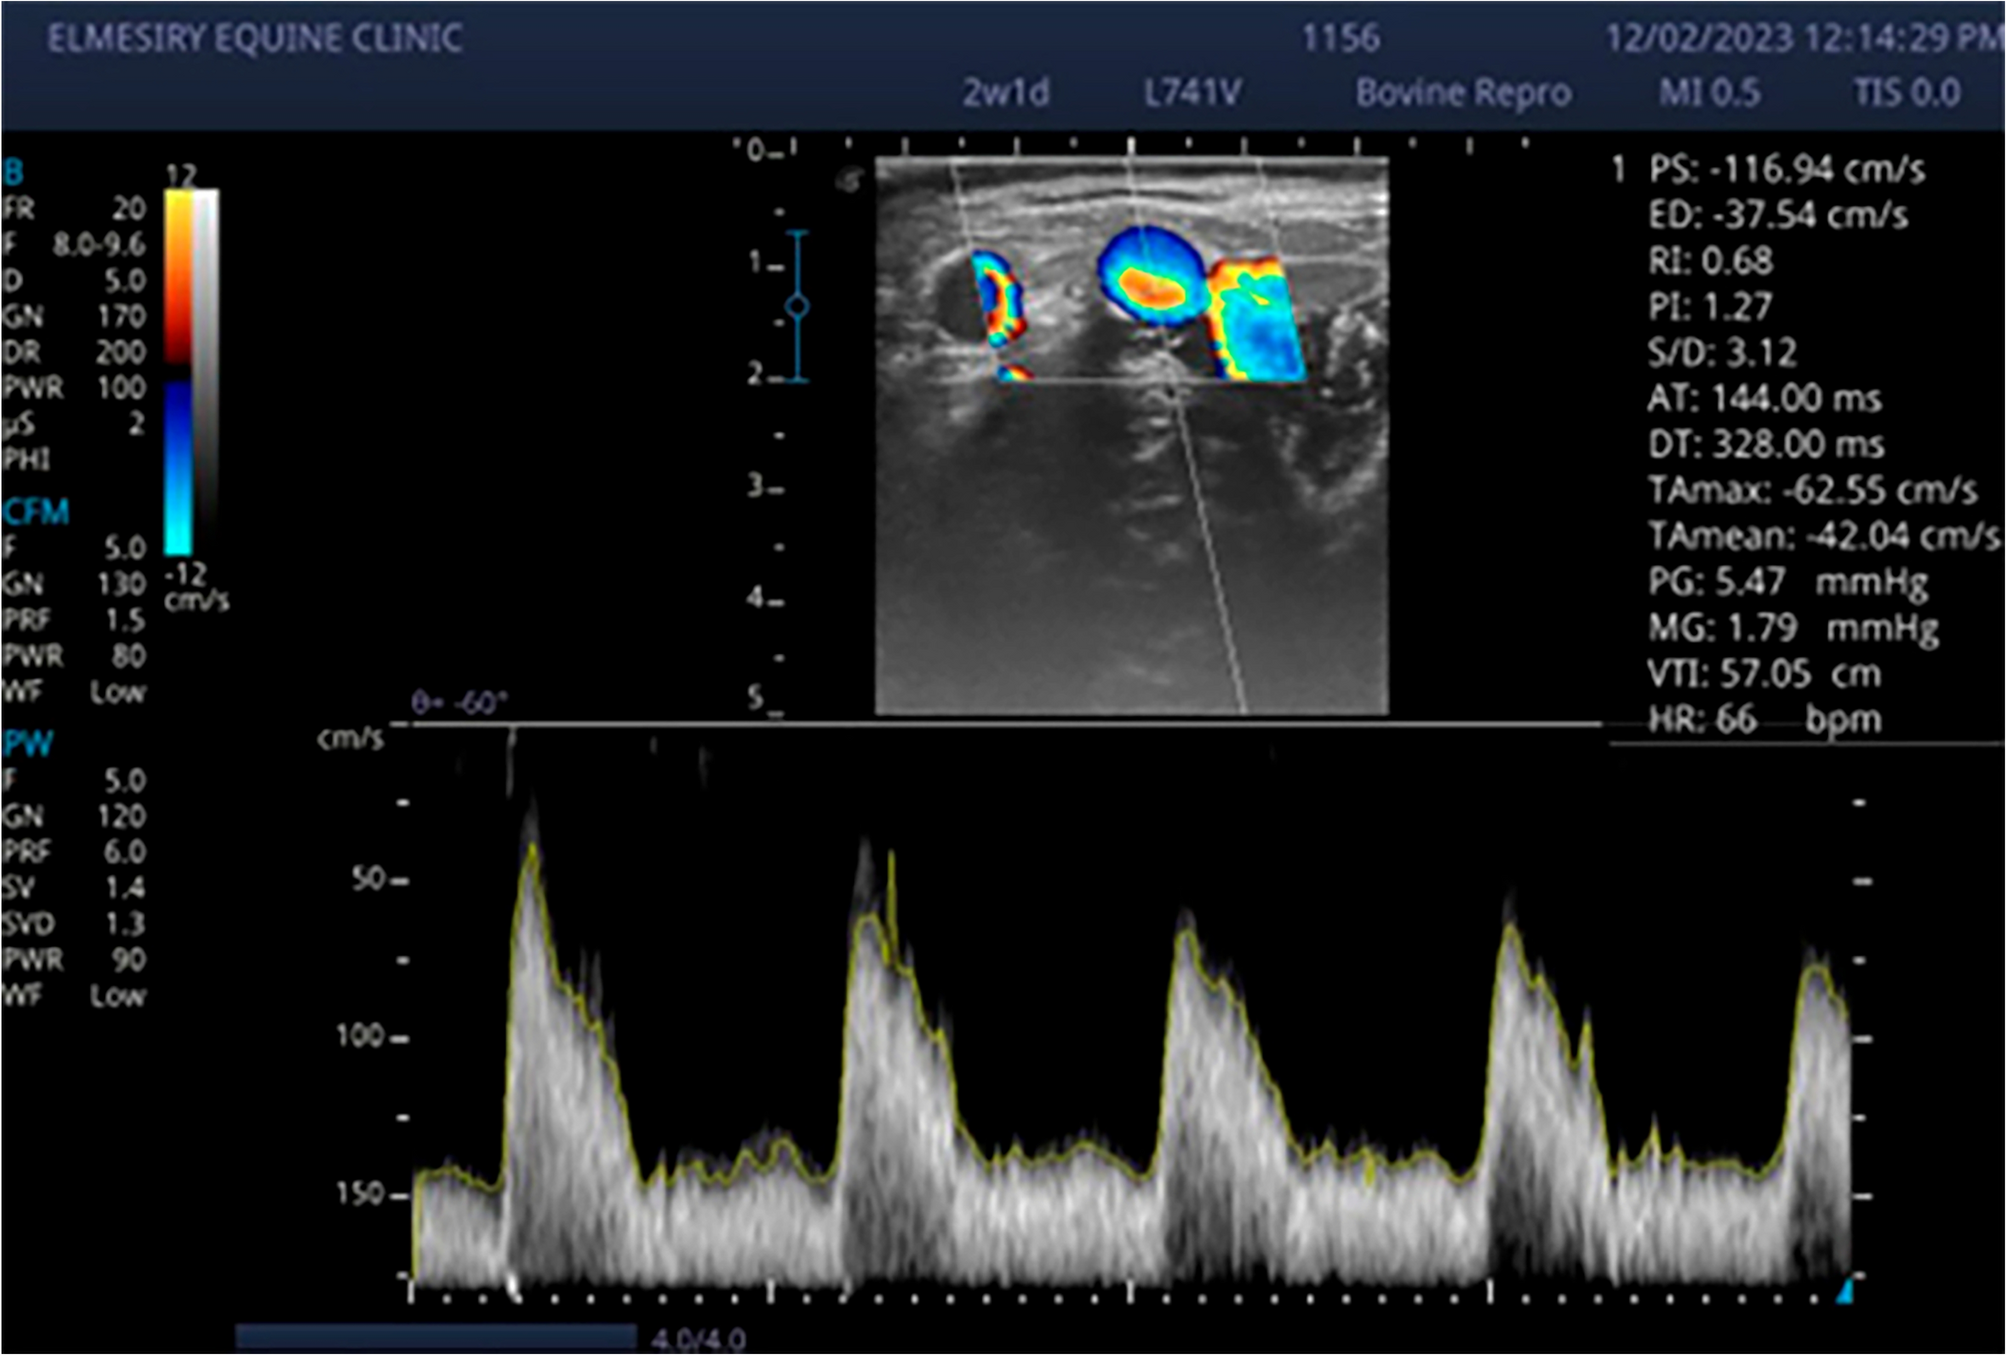

Figure 2

Doppler sonogram images illustrate waveform of at mid‐estrus buffalo cow; Waveforms diagnosed with clinical endometritis characterized by low RI and PI with significant (p < 0.05) increased of TAMEAN (cm/sec) and TAMAX (cm/sec).